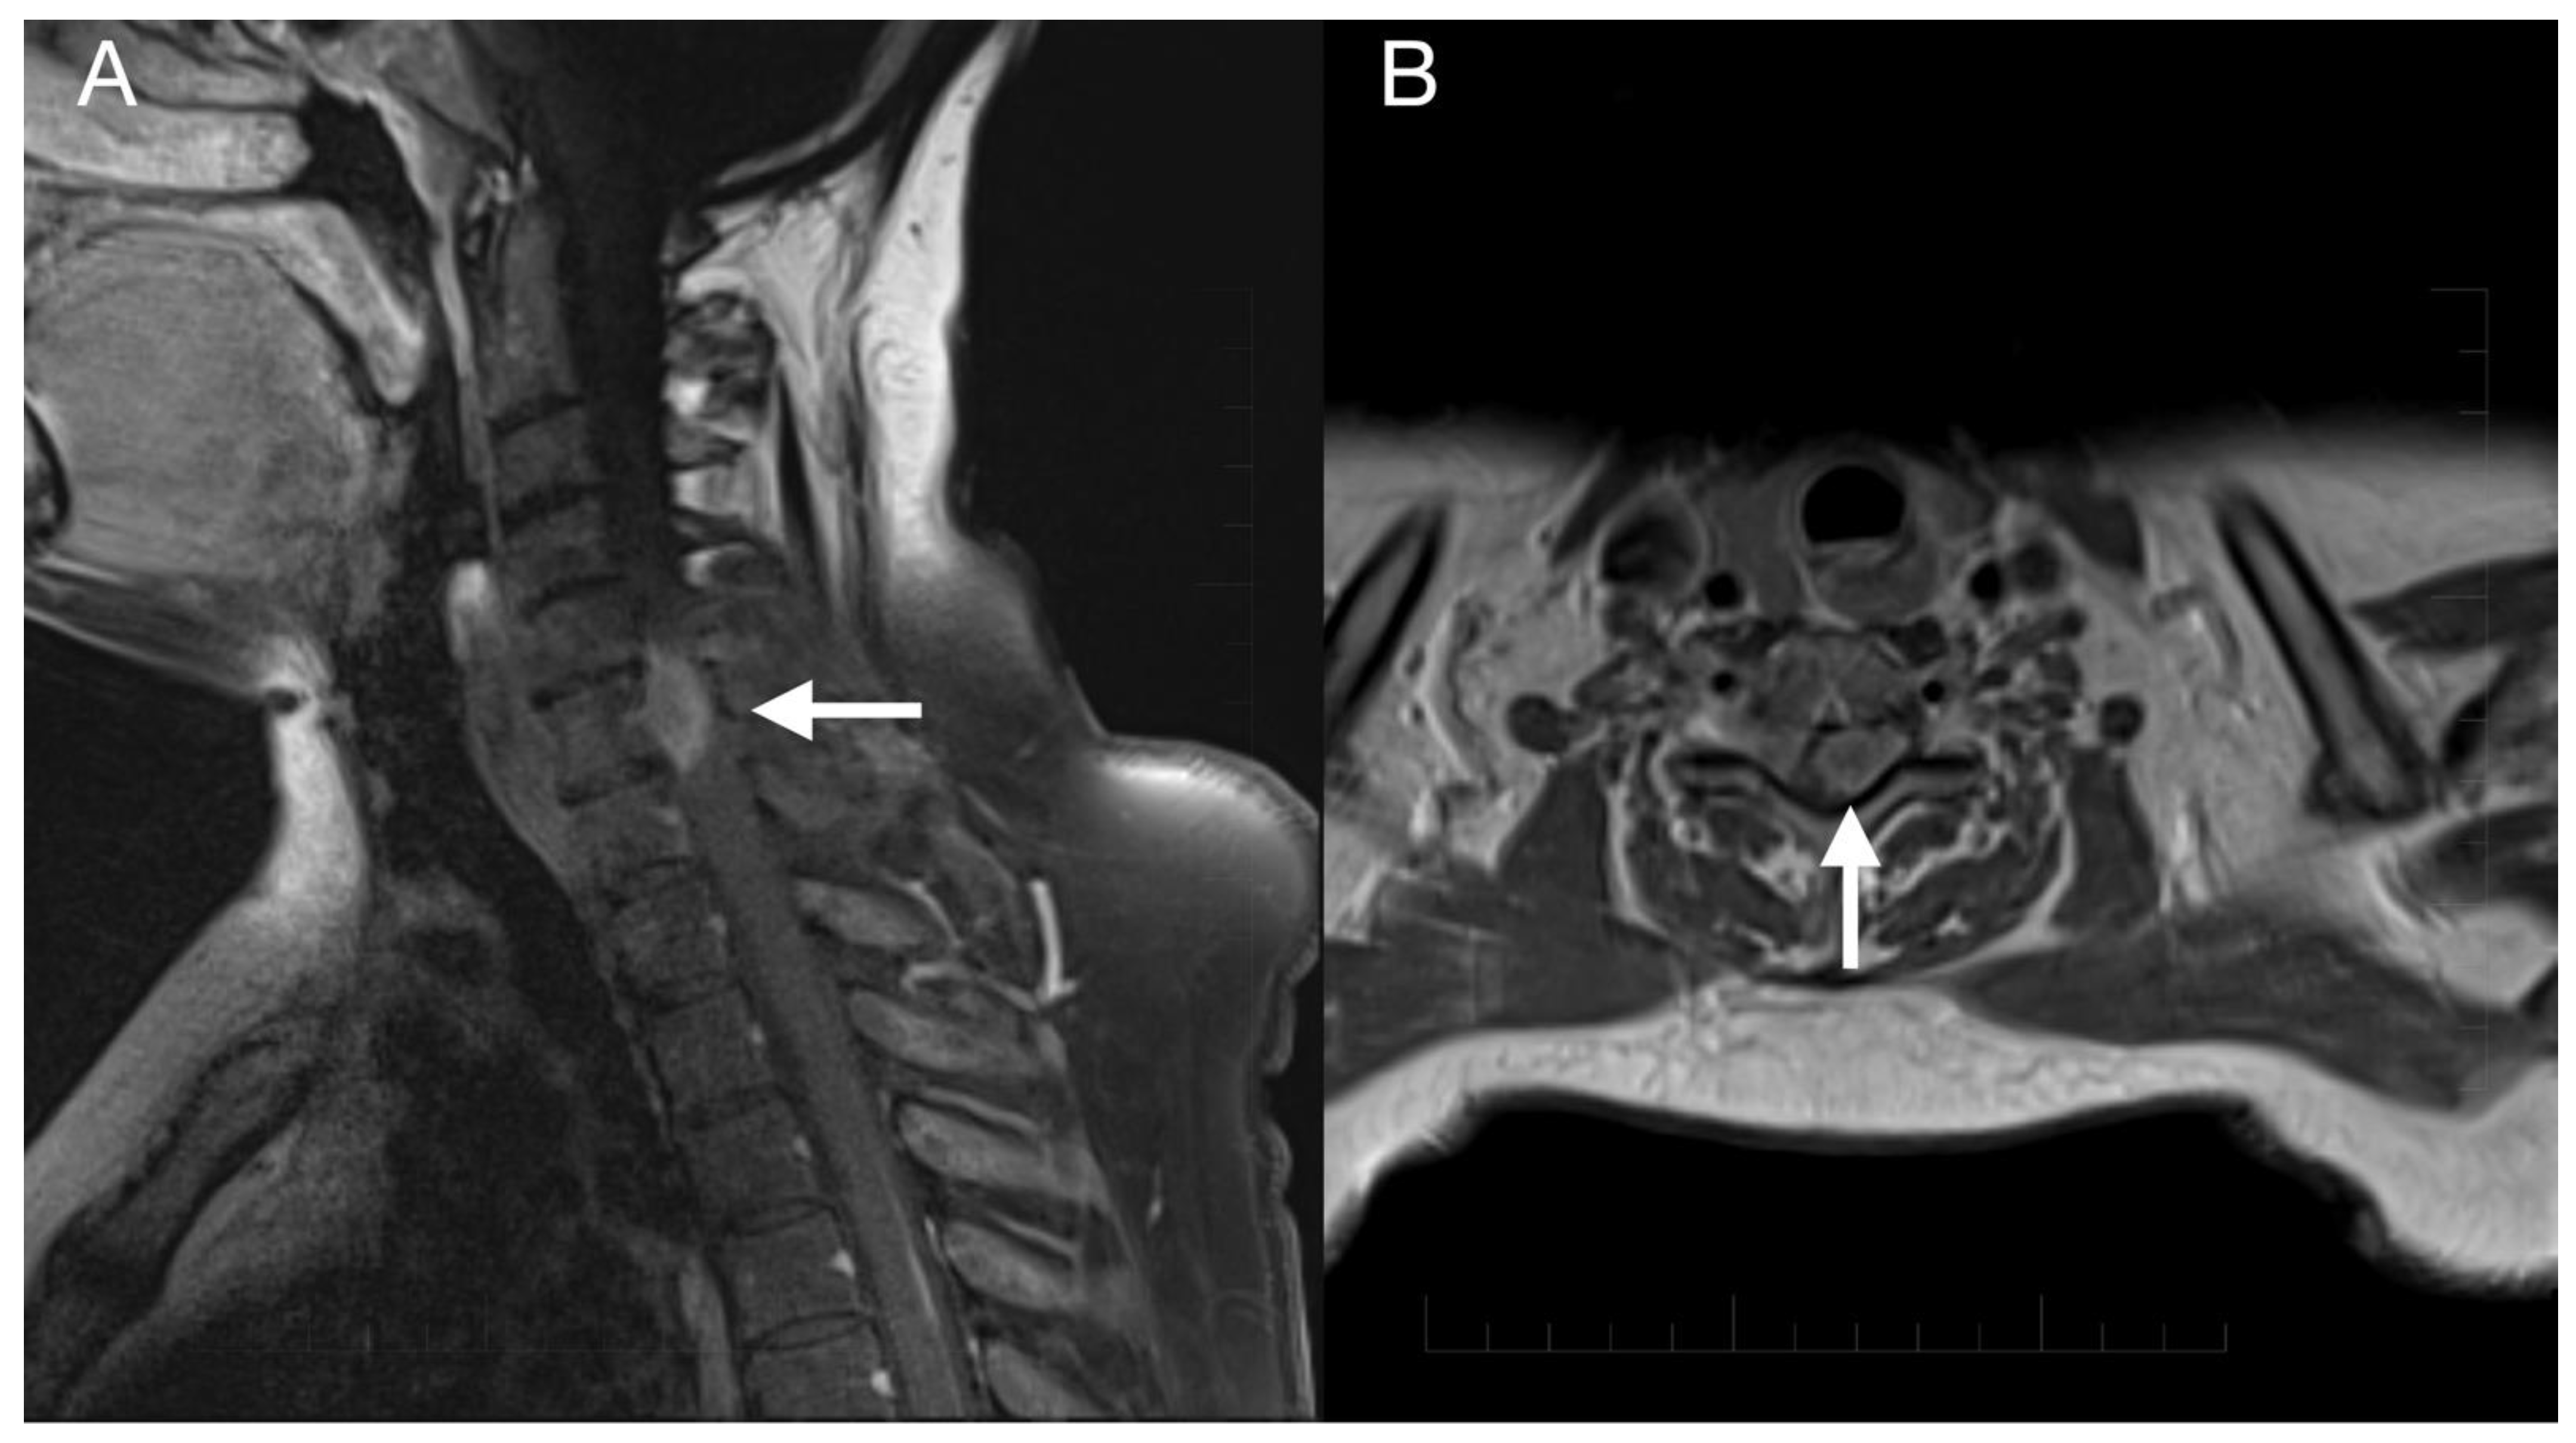

Imaging prior to the oncological treatment uncovered GBM’s rapid early progression [2] (Figure 4A and Figure 5A). The patient received standard focal radiotherapy plus concomitant daily temozolomide followed by adjuvant temozolomide. Fractionated conformal radiotherapy was delivered using the volumetric modulated arc therapy (VMAT) technique to a total dose of 60 Gy in 30 daily fractions of 2 Gy each. Concomitant chemotherapy consisted of oral temozolomide at a daily dose of 75 mg/m2 given 7 days per week from the first to the last day of radiotherapy. After a 4-week break, the patient underwent only two cycles of adjuvant oral temozolomide for 5 days (first cycle 150 mg/m2 and second cycle 200 mg/m2) every 28 days. Although no sign of further progression of residual intracranial GBM was seen on the follow-up MRI 3 months after chemo-radiotherapy (Figure 4B and Figure 5B), the patient presented with the sudden onset of quadriparesis and paresthesia of the trunk and all extremities shortly afterward (five months after the diagnosis was established). MRI examination of the spine revealed intradural extramedullary spinal expansion at the C6 level with spinal cord compression and edema (Figure 6 and Figure 7). Laminectomy of C5–C7 and decompression of the spinal canal with biopsy were performed since radical resection was not possible. Histopathological examination displayed hypercellular glial neoplasm formed by plumb epithelioid cells with abundant pale eosinophilic cytoplasm and prominent nuclear pleiomorphism alternating with small cells with minimal cytoplasm and dense nuclear chromatin (Figure 8A). Tumor cells expressed GFAP and neuron-specific enolase (Figure 8D,F). The diagnosis of metastatic GBM infiltrating both the dura mater and the spinal cord was made based on the clinical presentation as an intradural extramedullary mass and microscopic similarities in the primary and metastatic tumor. Despite the hypofractionated course of palliative radiotherapy on the area of intraspinal infiltration (20 Gy in 5 fractions), the patient’s neurological condition deteriorated, and she was transferred to a palliative care institution after two weeks. Finally, she succumbed eight months after the surgery for the brain GBM and less than three months after the spinal GBM metastasis occurred.

Figure 6.

Imaging of the spinal metastasis. Five-month postoperative cervical spine MRI (postcontrast T1 weighted images) showing intradural expansion (arrow) at the C6 level intimately related to the spinal cord with spinal cord compression (A). Axial section showing intradural expansion (arrow) partially encircling the spinal cord and spreading into the neural foramen (B).

Figure 7.

Imaging of the thoracic and lumbar spine. Preoperative MRI of the thoracic (A) and lumbar spine (B) did not show other pathological changes related to GBM metastasis.